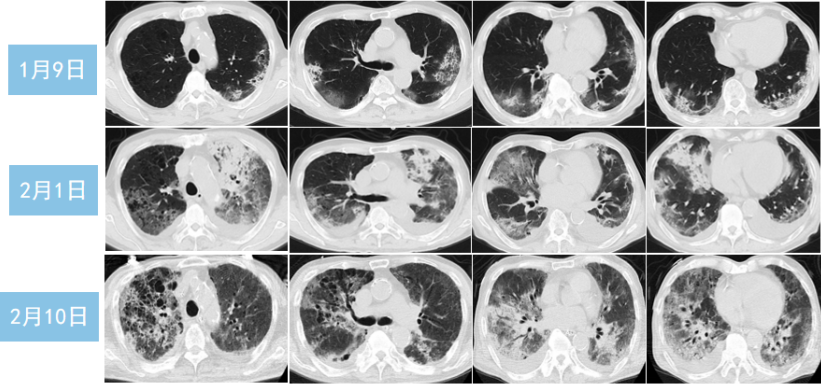

84岁男性患者,既往冠心病、陈旧性心肌梗死,未接种新冠疫苗。2022年12月15日起病,12月27日诊断为COVID-19,Paxlovid治疗5 d停用,同时抗炎。2023年1月9日肺部病变吸收,予以出院。

1月26日再次发热、呼吸困难加重,铁蛋白513.5 ng/ml,IL-6 3834.49 pg/ml。入院后细菌、真菌、病毒的病原学检查均为阴性,未找到继发感染的证据。ANCA+ANA、肌炎抗体谱均阴性。予甲强龙80 mg qd 3 d,后改为40 mg qd。治疗后炎症指标逐渐下降,影像学吸收。

图片

患者影像学变化

该患者第一次出院后应继续抗炎治疗,可能由于抗炎疗程不足,导致出现了炎症的“反弹”。